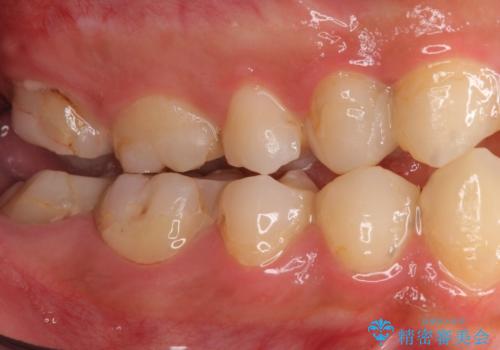

- 憧れの芸能人(ヴィジュアル系バンドマン)のような歯になりたいとのご希望で来院された患者様です。

咬み合わせが悪く矯正も検討されていたそうですが、歯を真っ白にしたいというご希望もあり、28本のすべての歯をセラミックにしたいとのことでした。

精査したところ、ほとんどの歯が保険内のレジンで充填されており、咬み合わせも悪く咬合していない歯もありました。

虫歯をしっかりと治療したのち、オールセラミッククラウンによる補綴治療を行いました。